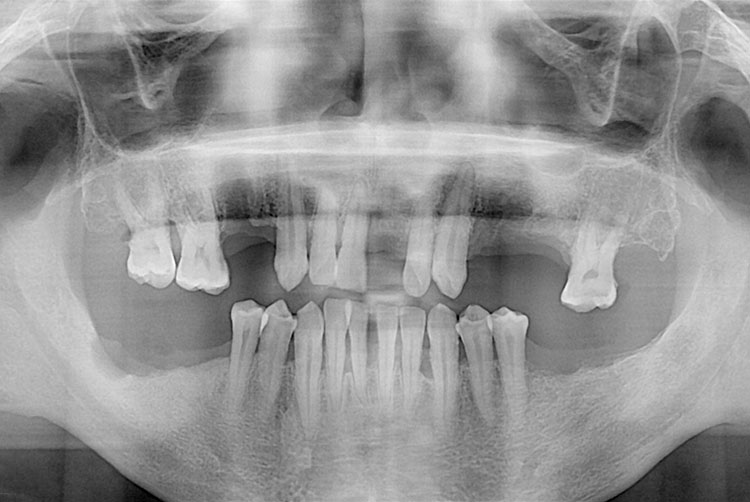

치료전 : 2018-05-14